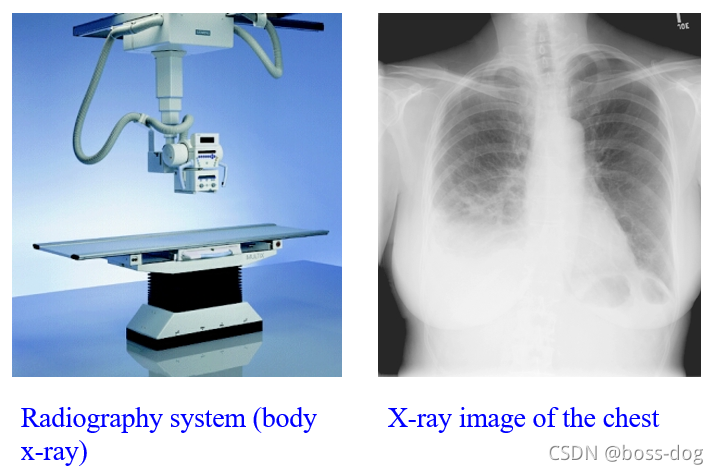

Radiography(X光成像)

上图中: